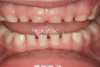

(19.) Five-year-old child with significant attrition. Mother reports a history of sleep bruxism (Case provided by Kathy French, DDS).

Figure 19

(20.) Maxillary anterior tooth wear. Adenotonsillectomy (T&A) performed and postoperative apnea-hypopnea index (AHI) was 6.1. Continued therapy recommended for resolution.

Figure 20